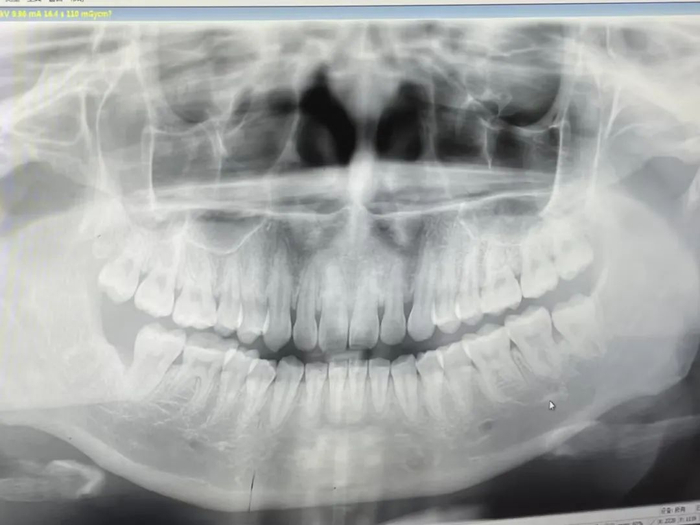

并不是所有的智齿都要拔除,但你的智齿要不要拔,还是得让牙医看完牙片说了算。

拔智齿怎么说也是个小手术,慎重一些也不为过。如果你纠结拔不拔智齿,不如上传牙片,让口腔科医生来判断,综合考虑各方面因素再做决定。

要不要拔智齿,什么时候拔最好,要拔几颗……每个人的答案都是不一样的。上传你的牙片,并详细描述你的牙齿情况,可以让口腔科医生帮你制定个性化的拔牙方案。